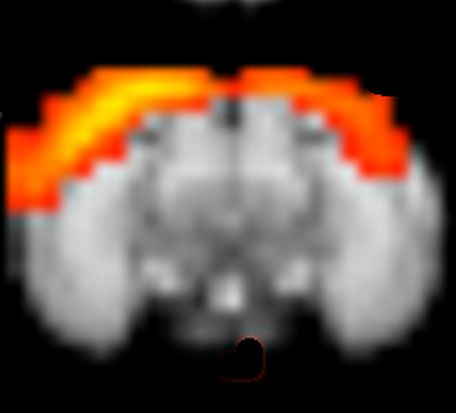

Diffusion Tensor MRI (DTI) and Resting State Functional MRI (rs-fMRI) are performed to compute the structural and the functional connectome under different environmental conditions (such as lighting, circadian rhythm, sleep cycle), age and sex, as well as under pathological conditions (models of infectious diseases) to elucidate possible confounding factors. Alterations in the functional connectome due to lesions of the structural connectome are predicted using “The Virtual Mouse Brain” model in collaboration with Christophe Bernard from the “Institut de Neurosciences des Systèmes”.